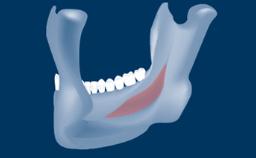

In this short microlearning module on digitally guided sinus floor elevation, we delve into a specialized aspect of the digital workflow for implant-guided surgery, focusing on the use of digital guides in the sinus floor elevation technique.